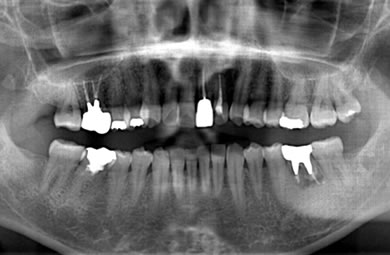

インプラントの症例写真 IMPLANT

インプラント治療+セラミック治療

| 治療方針 | 前歯部の審美的回復をセラミック治療で行う。臼歯部の審美的・機能的回復をインプラント治療で行う。 | ||||||||||||||||||||||||||||||||

| 治療内容 | インプラント1本、メタルボンドセラミック1本、オールセラミック2本(オールセラミック用の土台2本) | ||||||||||||||||||||||||||||||||